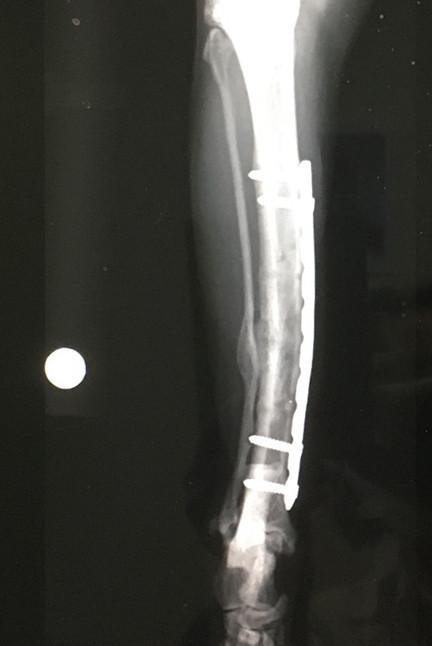

2021年4月、骨折してから9ヶ月&プレート抜去手術(1回目)から1ヶ月半経過しての検診に行ってきました。

前回抜いたボルトの穴はいい感じに塞がり始めてました。

いい機材を使ってるから?と思ってたらどうも2枚撮影してたようで・・・

今回2枚目を見せてもらいましたよ。

確かにこれはお医者の判断には必要でも素人にはわかりづらいので見せなくてもOKかもだけど

飼い主からしたらせっかくなら見せてよ!って思うですよ(^_^;。

まぁ結局見せてもらってもようわからんですけどw。